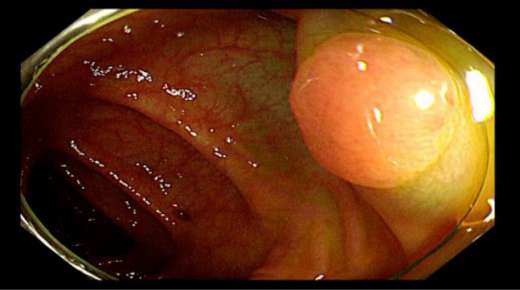

距肛门16cm直肠白光下较大息肉在检查过程中我们发现,C先生在升结肠回盲瓣附近、横结肠、直肠等部位多发息肉,个别息肉较大,甚至达到1.5cm以上。且通过NBI技术进行观察,息肉已经有了病变的不良趋势。

横结肠白光下息肉,基底部给予亚甲蓝生理盐水黏膜下注射后拟行EMR(内镜下黏膜切除术)术